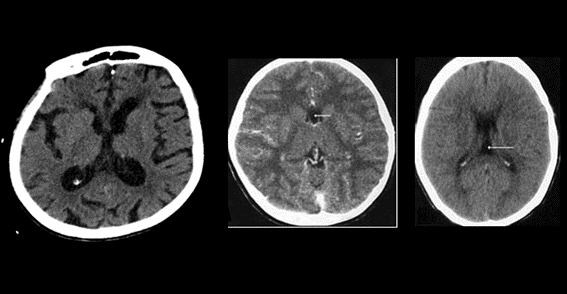

Encontramos como primer error el volumen parcial dado por estructuras vecinas, es frecuente con las estructuras óseas

Los lóbulos temporales y fosa posterior son afectados por artefactos de endurecimiento del rayo y se aprecian como zonas de hipodensidad irregular y no debe confundirse con gliomas. Se diferencian por la falta de masa.

Fig. 10.

Fig. 9.

Medios de contraste

Se pueden apreciar imágenes que pueden confundirse con aneurismas o malformaciones vasculares, pero al detallarse en otro plano (coronal), las  identificamos como  variantes anatómicas como elongaciones, bifurcaciones ,  anomalías venosas del desarrollo o vasos tentoriales.

Fig. 11.